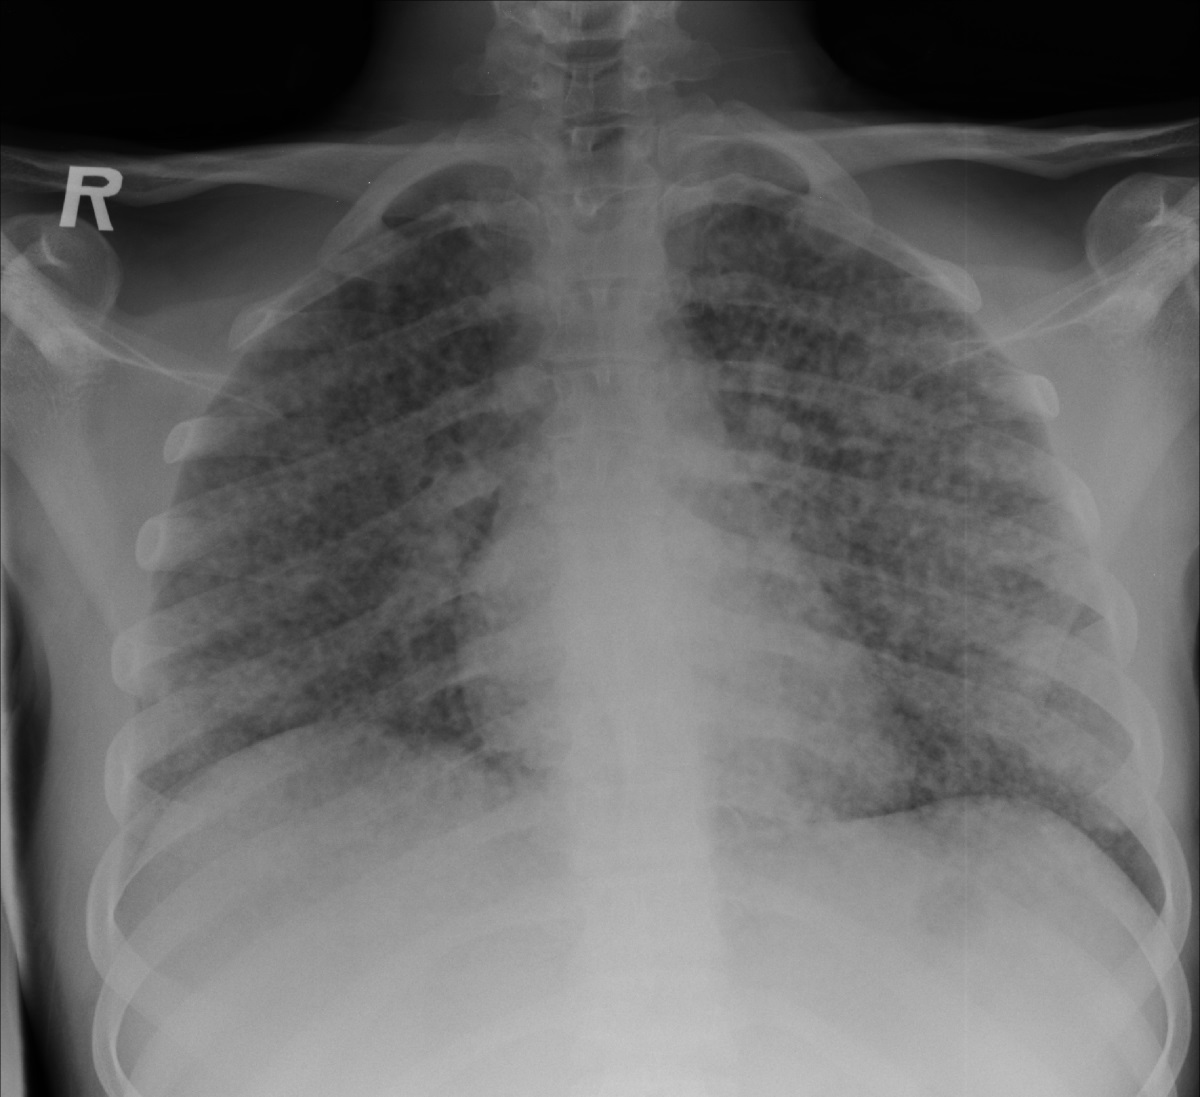

Severe disease with poor immune response can produce a picture like millet seeds over the CXR.